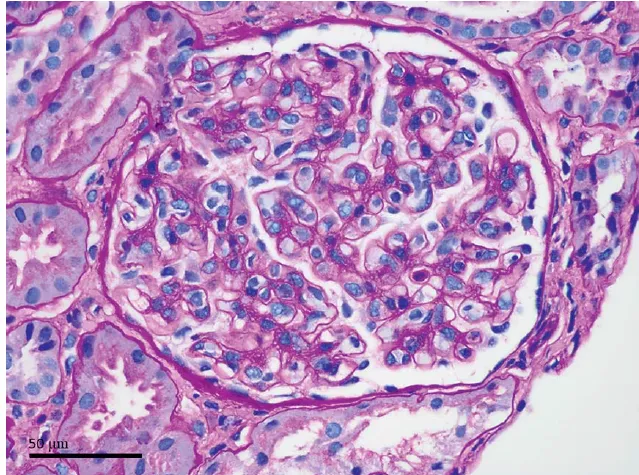

Biópsia renal: infiltrado intersticial mononuclear denso com eosinófilos e sem fibrose significativa.

3. A biópsia mostra inflamação ativa, com pouco ou nenhum grau de fibrose.

Quanto antes o corticoide for iniciado após a identificação de NIA sem fibrose (idealmente nas primeiras 2 semanas de lesão renal), maior a chance de recuperação completa da TFGe!

Se a creatinina está subindo, a droga suspeita já foi suspensa, e a biópsia mostra inflamação ativa sem fibrose... Não perca tempo! O corticoide pode evitar a evolução para DRC e até tirar o paciente da diálise!